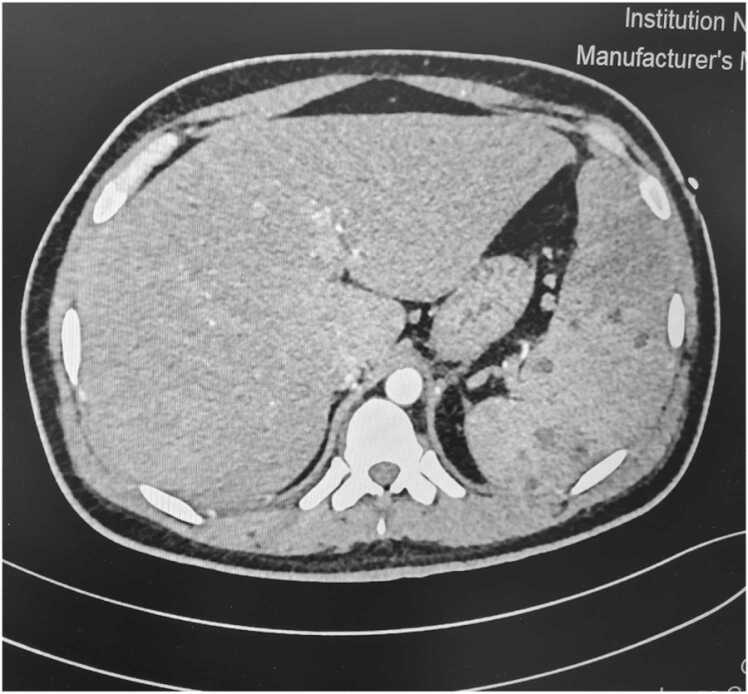

On arrival to ICU he was started he was started on NIV support in view of respiratory distress and low saturation with settings of FiO2 0.8, PEEP 8 cm H2O and PS above PEEP 12 cm H2O. Urgent USG abdomen showed hepatomegaly with right lobe live liver abscess and splenic abscess. Provisional diagnosis of sepsis with MODS (? Melioidosis) with diabetic ketoacidosis was made. Blood, urine, sputum cultures were sent before starting the antibiotics. The patient was started on meropenem, metronidazole, teicoplanin, doxycycline, low molecular weight heparin (LMWH) and i.v. insulin infusion. Further investigations showed areas of consolidation and diffuse ground glass opacities in bilateral lung fields in HRCT chest (Fig. 1). CECT abdomen revealed multiple liver abscess in right lobe of liver, multiple splenic abscesses with hepatosplenomegaly (Fig. 2). Diagnostic tap of liver abscess was sent to confirm the diagnosis and ensure long term compliance of the patient with the oral antibiotics to be given for the eradication regime of Burkholderia pseudomallei.

Fig. 1.

HRCT chest of case 1- Consolidation and ground glass opacities in bilateral lung fields.